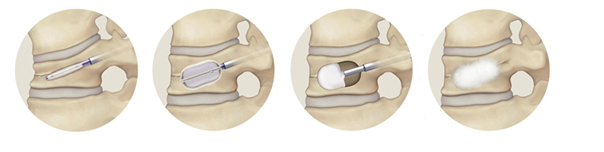

経皮的椎体形成術(Balloon Kyphoplasty:BKP)

適応:胸椎・腰椎圧迫骨折

脊椎圧迫骨折は強い痛みを伴い、骨がさらに潰れるのを防ぐために、何週間もベッド上での安静が必要となることがあり、寝たきりになる可能性があります。当院では経皮的椎体形成術を早期に行うことで痛みを軽減し、できるだけ早くに普段の生活に戻っていただくことを目指しています。手術は全身麻酔下で20分ほどで終了します。背中から細い針を骨折した背骨に刺し、歯科治療でも使われる医療用の骨セメントを注入して補強します。術後は翌日より歩行を開始し、多くの患者さんは1週間後のレントゲン検査で問題がなければ退院となります。

骨折椎体内でバルーンを膨らませ、空間を作ってからセメントを注入します。